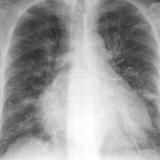

CHF progression

Date: 11/05/2005

Views: 3430